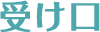

治療方法 マウスピース型矯正装置

(インビザライン)治療の説明 主訴:叢生 年齢 32歳 抜歯箇所 なし 治療期間 1年1ヶ月 通院回数 10回 ![]()

治療費用 767,800円 治療の内容・詳細 初回と追加アライナーで主訴の叢生を改善、最終左上2番の挺出と嚙み合わせの調整を行い治療を終了いたしました。 治療の副作用(リスク) 保定装置をしっかり装着していないと、後戻りする可能性があります。咬合痛、歯根吸収、歯根露出を生じる可能性があります。